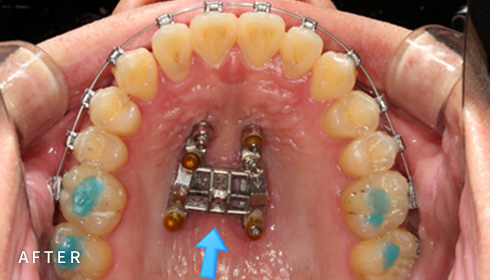

안보이게 아름답게

설측교정

아름다운 미소를 만드는 고난이도 프리미엄 교정 치료입니다.

난이도가 높은 만큼 풍부한 진료 경험이 중요합니다.

강남에서 다년간 설측교정에 특화된 경험을 바탕으로,

3D 디지털 기술을 활용한 맞춤 설계, IDBS방식을 통한

정밀하고 불편감 없는 치료를 제공합니다.